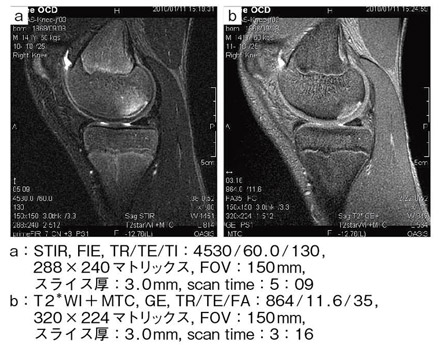

【RAPID KNEEコイルによる膝関節の離断性骨軟骨炎】